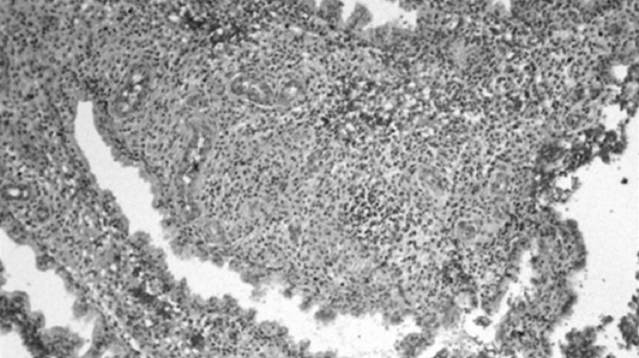

При анализе результатов иммуногистохимического исследования выявлено наличие как аутоиммунного хронического эндометрита, так и хронического эндометрита без аутоиммунного компонента. При исследовании рецепторного статуса эндометрия у женщин с бесплодием обнаружено, что хронический эндометрит сопровождается снижением экспрессии эстрогеновых рецепторов в железах как в фазе пролиферации, так и в фазе секреции, в строме — преимущественно в фазе секреции (рис. 1). Экспрессия прогестероновых рецепторов в железах и строме эндометрия снижается в фазе секреции (рис. 2).

Рис. 1. ER-рецепторы

Рис. 2. PR-рецепторы